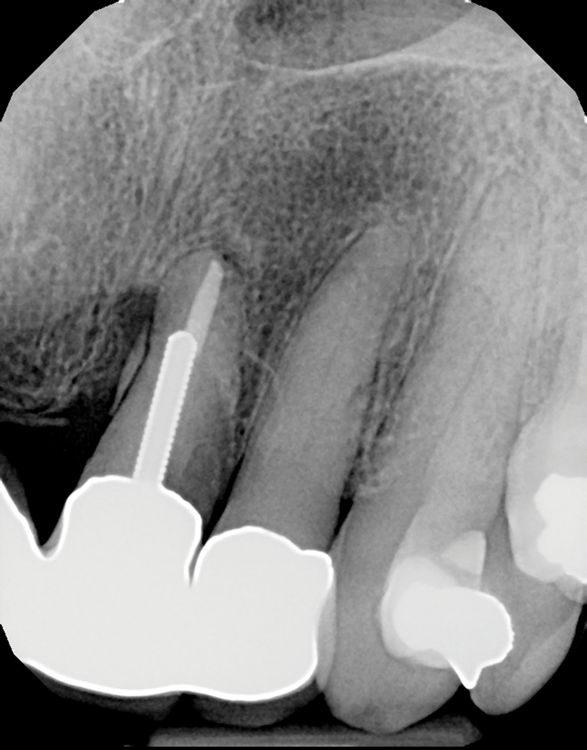

(3.) Radiograph of a loose screw-style metal post.

Figure 3

(4.) Radiograph of a root fracture that occurred at the end of a parallel metal post.

Figure 4